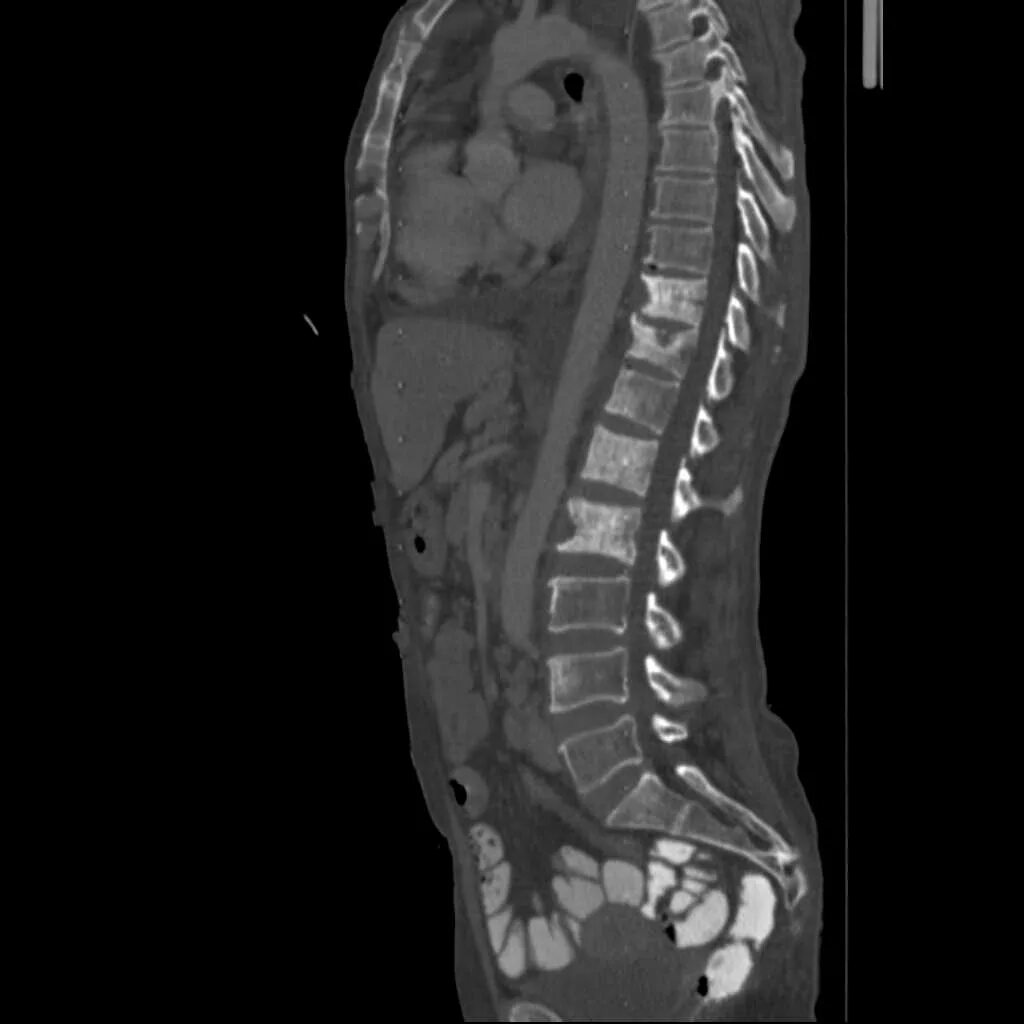

Метастазы костей мрт